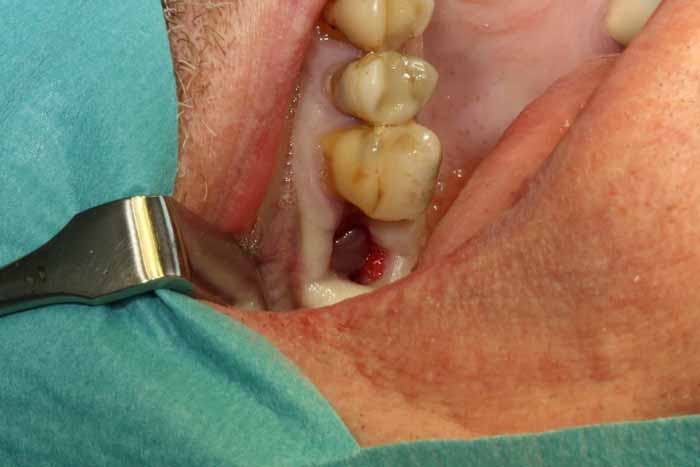

原因

上顎小臼歯と大臼歯の歯根は副鼻腔底に近くにあり、根尖性歯周炎では骨の境界が緩み、細菌が上顎腔に侵入して副鼻腔炎を引き起こす可能性があります。抜歯、顎外科手術、インプラント埋入では、口腔と上顎洞の間に急性的な交通路が残ることがあります。その結果、いわゆる口腔前庭部に口腔上顎洞瘻を形成し、そこから膿が排出され、それが副鼻腔への微生物の侵入点となり、細菌の定着や感染につながる可能性があります(画像2a、2b)。

治療

慢性副鼻腔炎の治療には、歯の感染の除去が含まれます。これには、歯内療法、歯周治療、または外科的な処置による抜歯が必要になる場合があります。感染の予防が困難な場合は、抜歯が必要になる場合があります。その後、副鼻腔の交通を特定するために、Vamevalテストを実施する必要があります。患者との良好なコミュニケーションが極めて重要であり、治癒を確実にするためには、より根本的な治療が必要になる場合が多いです。急性副鼻腔炎の場合は治療が必要です。PC予防と、ネザリルなどの充血除去薬を組み合わせた、1回限りの手術が行われる。より大きな交通や瘻孔が慢性化している場合は、鼻の矯正手術(画像4a~4e)が必要となります。場合によっては、耳鼻咽喉科医によるFESS手術と同時に行うこともできます。FESS手術では、鼻の側壁にある開口部を外科的に広げて換気を確保し、閉塞を防止します。

歯が原因となって菌の活動が活発になっていると思われる副鼻腔炎(保健センター/耳鼻咽喉科クリニックでのCT検査によって確認されたものなど)の場合、抜歯前に綿密な治療計画を立てる必要があります。抜歯後の副鼻腔閉鎖時に、副鼻腔内にまだ膿性浸出物が残っており、活動性の感染症がある場合には、交通路の形成が優れた技術的品質で実施されたとしても治癒の条件は悪くなります。副鼻腔閉鎖時には、感染を軽減し、副鼻腔から膿性浸出物を除去する必要があります。これは、抜歯3日前に抗生物質治療を開始することで達成できます。抜歯中は、患者が座った状態で鼻/口から透明な液体だけが出てくるまで、生理食塩水で副鼻腔を洗浄します。